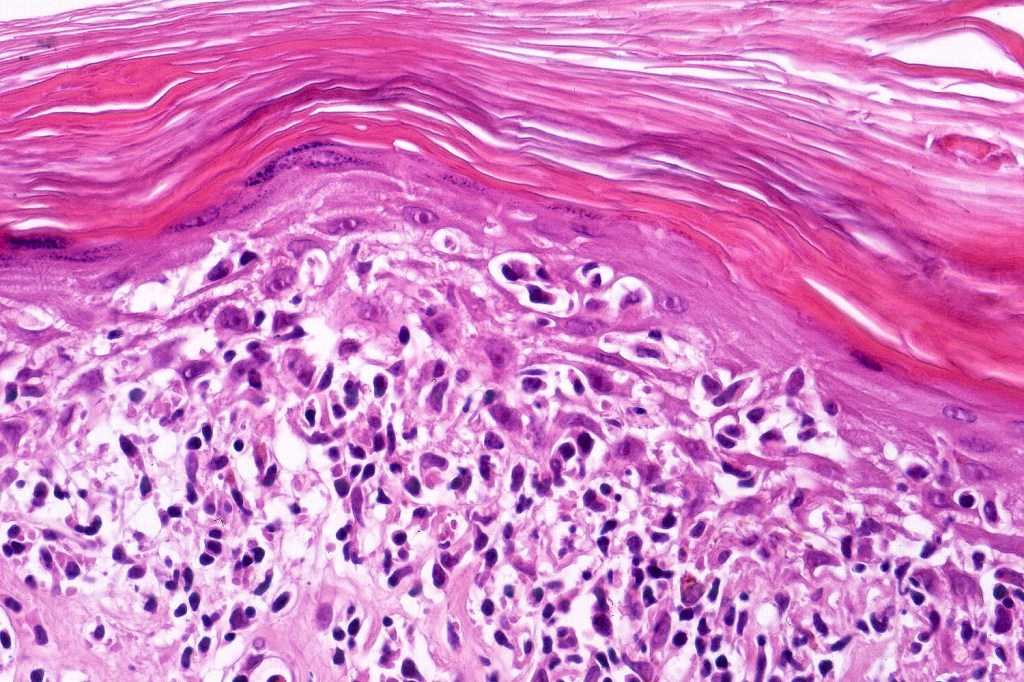

Histological features

The histological hallmark of mycosis fungoides is the presence of large atypical lymphocytes with a convoluted/cerebriform nuclear border (Sézary cells). These may be found at the epidermal-dermal jnuction and as collections within the epidermis (Pautrier microabscess). These are most easily found in plaque stage disease. The epidermal component can be subtle in patch stage disease and is often lost in tumor stage dsease. The classification into patch, plaque & tumor stage disease is less helpful histologically as the features merge from one to the other. It is all a matter of degree.

Patch stage disease

•Changes can be subtle & dependent on clinicopathological correlation; in many patients sequential biopsies over many months may be necessary to establish the diagnosis.

•Mild hyperkeratosis & focal parakeratosis, acanthosis, epidermal atrophy or of normal thickness

•Superficial dermal lymphocytic infiltrate containing variable numbers of Sézary cells with atypical, irregular, hyperchromatic nuclei surrounded by a halo; these can be very few in number and dependant on viewing multiple levels

•Palisading of atypical lymphocytes along the epidermal-dermal border

•Pautrier microabscesses may be present but are often absent in patch stage disease

•Variable interface change with keratinocyte necrosis & pigmentary incontinence

•Eosinophils & plasma cells sometimes present

•Coarse collagen bundles in the papillary dermis can be a feature but this is not as marked as seen in plaque disease

.Although in typical mycosis fungoides fungoides, spongiosis is absent, exceptionally it can be a feature